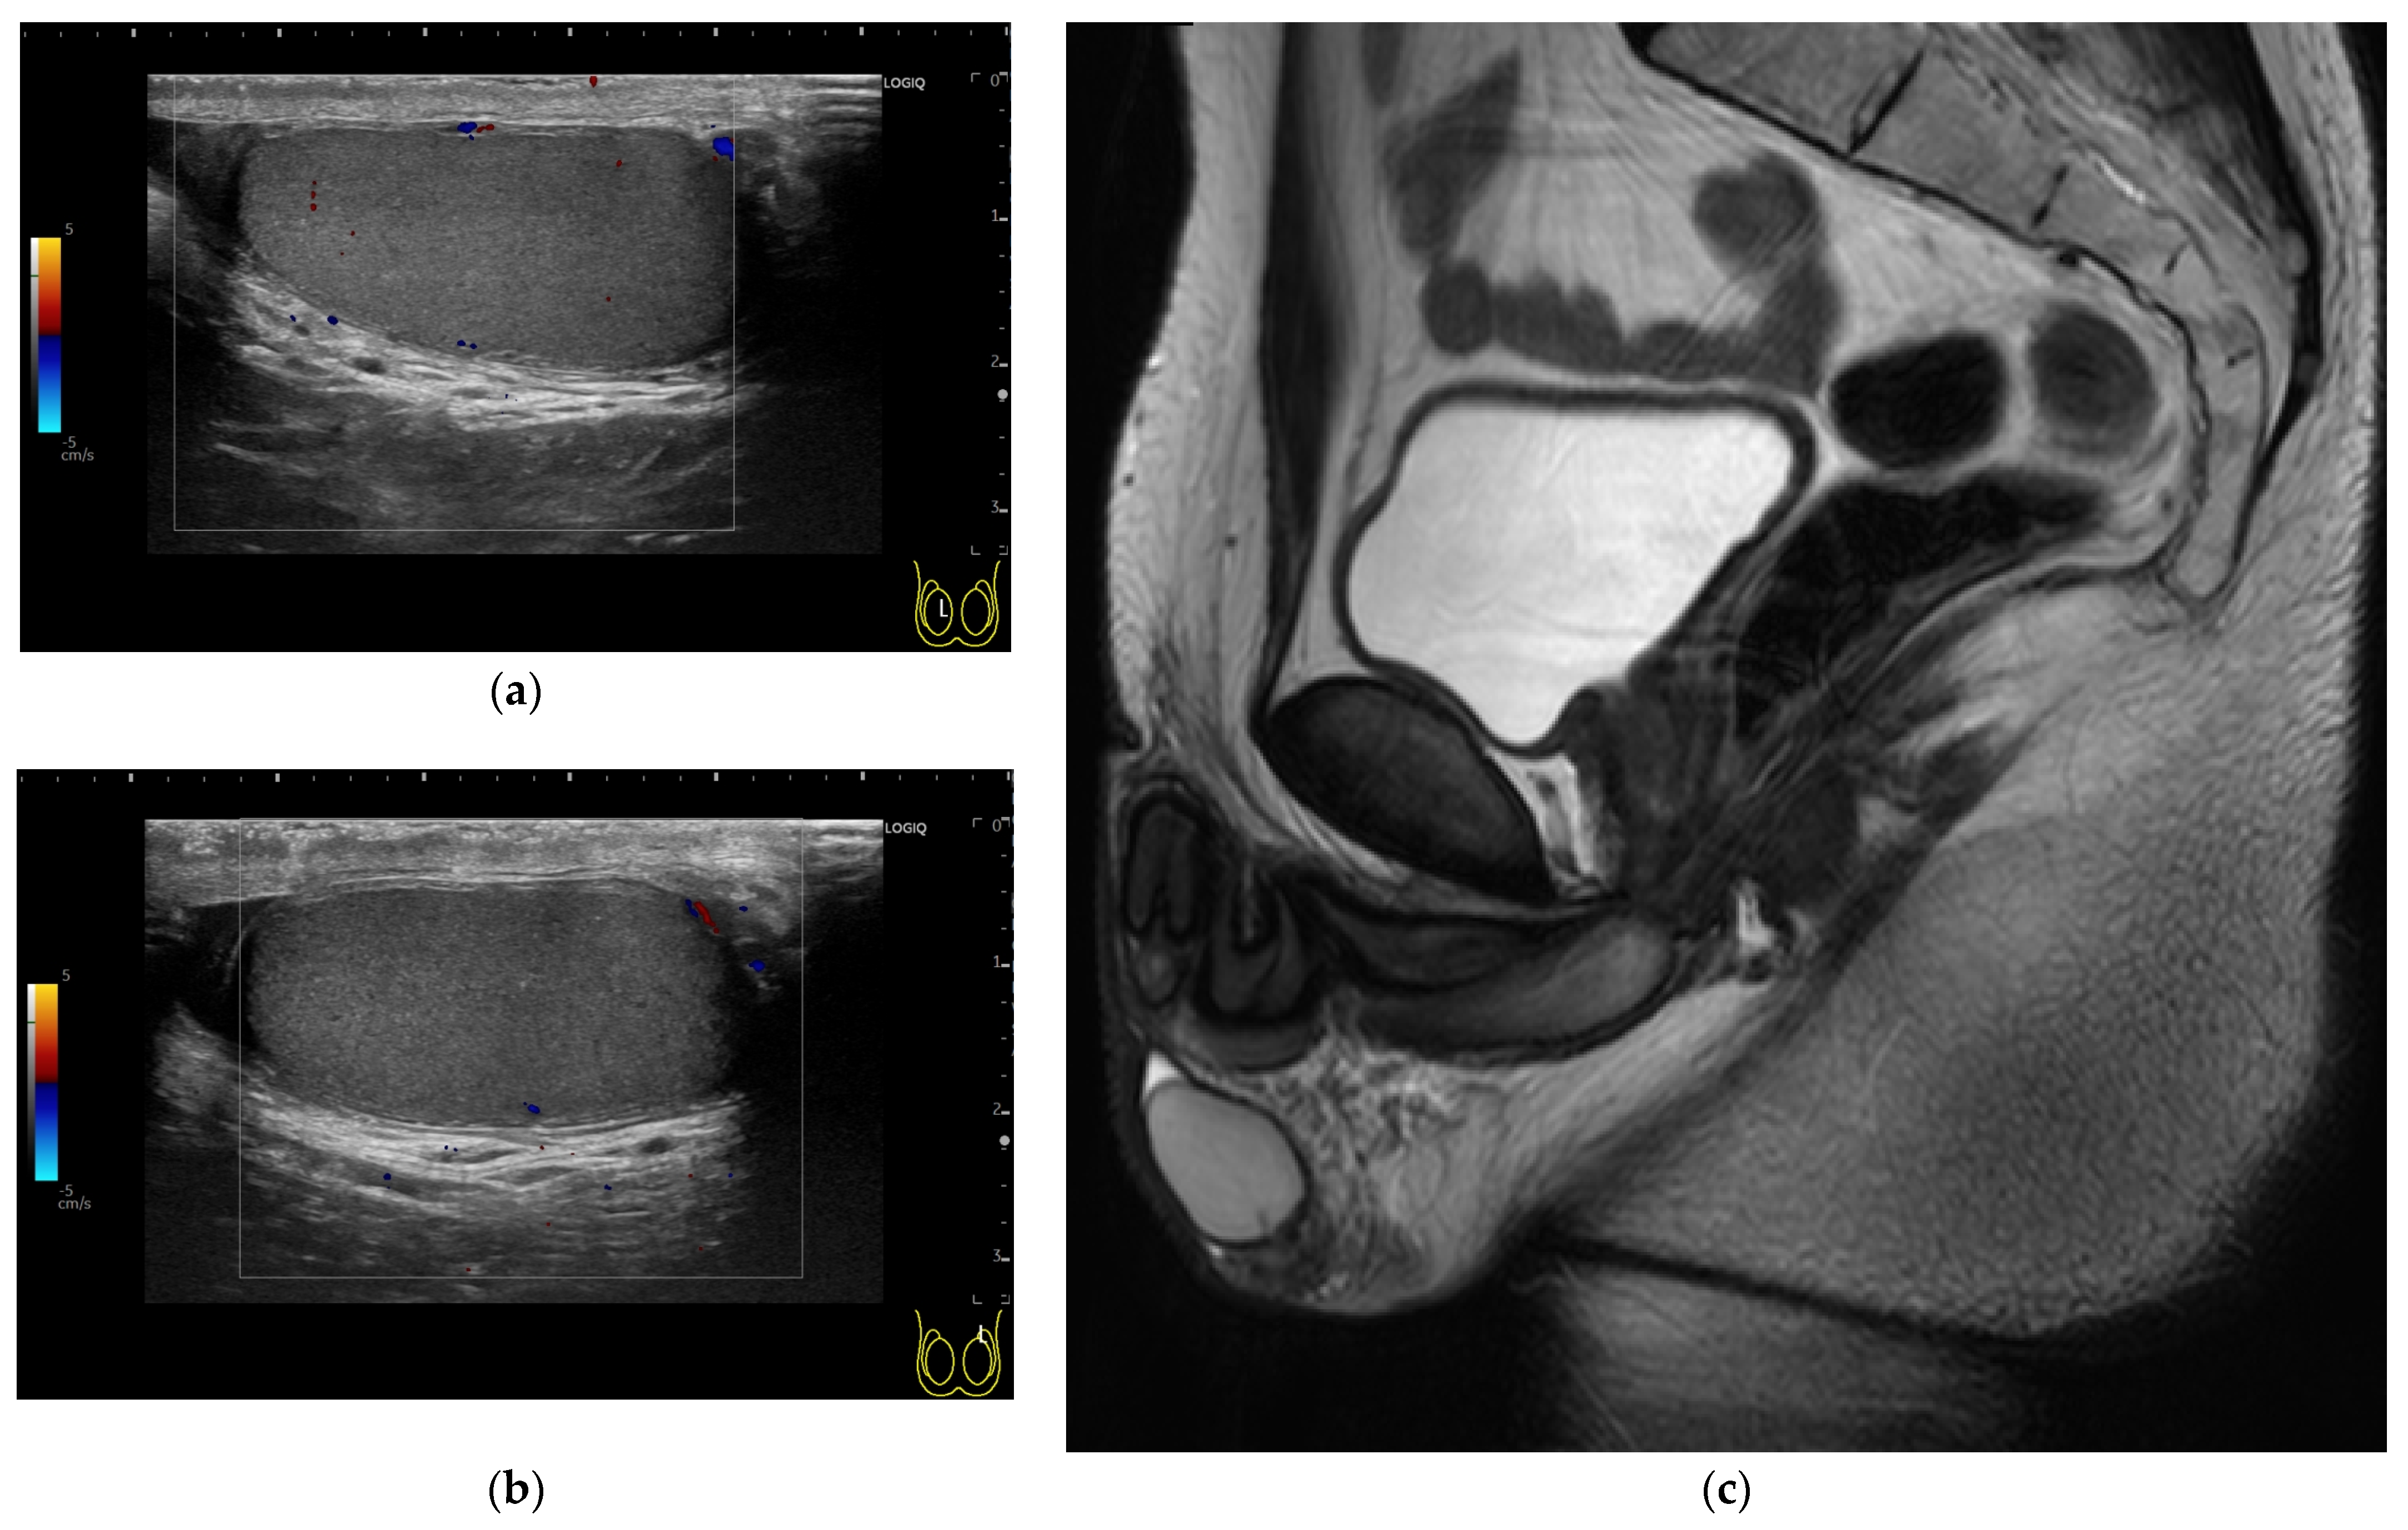

2. Case Presentation